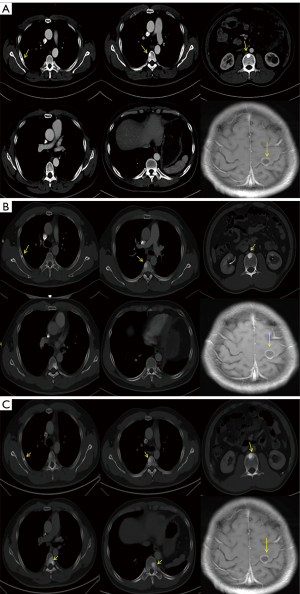

A 30-year-old non-smoking Chinese male was admitted to the First Affiliated Hospital of Nanjing Medical University on April 2020 presenting with several months of cough. Chest CT scans showed nodules in the lower left lung, indicating a high possibility of malignancy. On May 13, 2020, the chest CT scan showed a high-density mass in the left lower lung lobe, with a size of 2.6 cm × 2.1 cm. No obvious lymph nodes were observed in mediastinum, hilum of lung and axilla. Then, thoracoscopic left lower lobectomy with lymph node dissection was performed at the First Affiliated Hospital of Nanjing Medical University. Postoperative pathology showed that it was invasive adenocarcinoma with a mass size of 3.5 cm × 2.5 cm × 2.0 cm, stage IIIA (pT2N2M0) (Figure 1). The results of immunohistochemistry (IHC) were CK7 (+), TTF-1 (+), Napsin A (+), P40 (−), and Syn (−). However, a month later, brain magnetic resonance imaging (MRI) showed brain metastases. The patient then received first-line chemotherapy based on pemetrexed (900 mg d1) and nedaplatin (60 mg d1,2) on June 2020. With informed consent, DNA based 1021-gene panel sequencing was performed for lung tissue and paired leukocytes. A total of 6 somatic mutations were detected (Table 1), including SLC34A2-ROS1 fusion and NBN gene germline mutation. Thus, the patient received crizotinib in combination with pemetrexed and nedaplatin from July to August 2020. On September 2020, whole-body emission computed tomography (ECT) showed multiple bone metastases throughout the body, while the brain MRI showed the size of brain lesions was reduced. The overall efficacy was evaluated as progressive disease (PD). Then, the therapeutic regimen was switched from crizotinib to ceritinib, a second-generation ALK tyrosine kinase inhibitor. The patient received ceritinib combined with docetaxel as second-line therapy. After 2 cycles, the disease was assessed as slight progression. Due to sintilimab being approved for NSCLC, the patient requested to be treated with sintilimab. Considering the results of a large clinical study of sintilimab combined with chemotherapy in the first-line treatment for locally advanced or metastatic NSCLC (5), the regimen was adjusted to ceritinib, docetaxel, and sintilimab for 1 cycle on November 2020. On January 2021, cervicothoracic and abdominal CT and liver MRI showed multiple intrahepatic metastases. The condition was assessed as PD (Figure 2A). Considering that this patient carried ROS1 fusion and NBN germline mutation, and the literature review suggested that niraparib could be effective against tumor cells with HRR gene mutation and improve the efficacy of PD-1 inhibitors, we fully communicated with the patient before signing the off-label consent, then the regimen was adjusted to niraparib (200 mg/day) combined with docetaxel and sintilimab (200 mg Q3W) for 6 cycles. The patient was evaluated for efficacy in the second, fourth, and sixth cycles. The best curative effect was that the brain lesion was reduced by 18%, multiple lymph nodes around the bilateral axilla, neck and abdominal aorta were roughly similar than before. So, the overall efficacy evaluation was SD. (Figure 2B). He subsequently received sintilimab combined with niraparib maintenance treatment until November 2021, and the disease progressed at this time (Figure 2C). The 12-month landmark PFS rate was observed with the combination of sintilimab and niraparib. His treatment was then switched to sintilimab combined with niraparib, albumin-bound paclitaxel, and recombinant endostatin, and is currently still ongoing at the time of writing. In other words, at the end of the 23-month follow-up, the patient was still alive, during which CT and MRI scans were reviewed every 2 months. The major AEs observed were lymphopenia, nausea, vomiting, and edema. The treatment processes of this patient are shown in Figure 3.